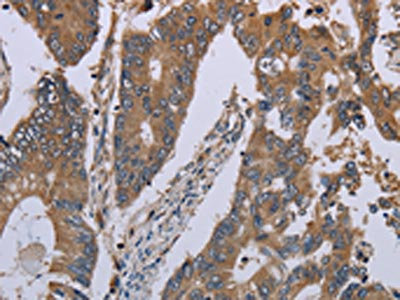

The image on the left is immunohistochemistry of paraffin-embedded Human colon cancer tissue using CSB-PA069966(NLRP12 Antibody) at dilution 1/30, on the right is treated with synthetic peptide. (Original magnification: ×200)

The image on the left is immunohistochemistry of paraffin-embedded Human liver cancer tissue using CSB-PA069966(NLRP12 Antibody) at dilution 1/30, on the right is treated with synthetic peptide. (Original magnification: ×200)